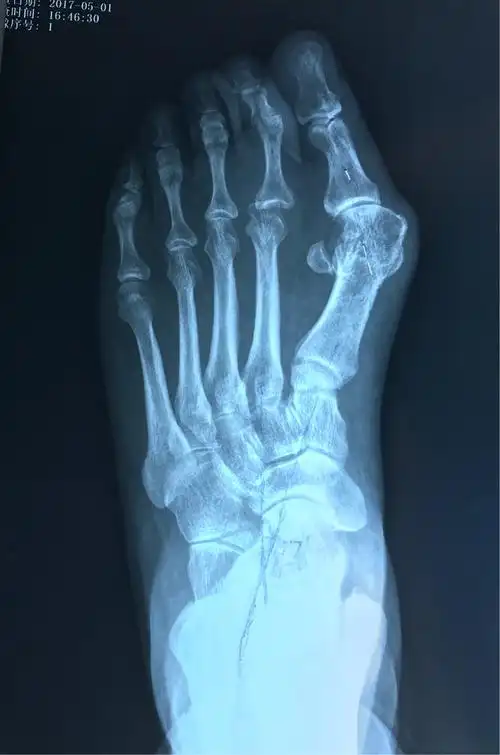

拇外翻矫正术 银川市第一人民医院骨科手足踝组 梁志军吕国栋